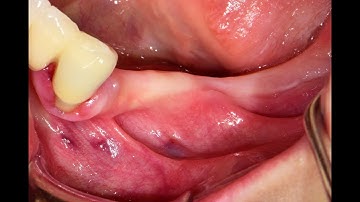

Horizontal Ridge Augmentation with Ti Mesh and Simultaneous Implant Placement